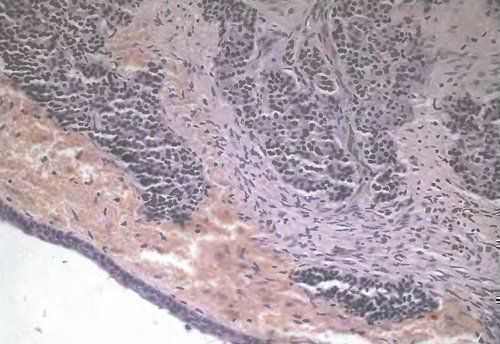

ΠΠΈΡΡΠΎΠ»ΠΎΠ³ΠΈΡΠ΅ΡΠΊΠ°Ρ Ρ Π°ΡΠ°ΠΊΡΠ΅ΡΠΈΡΡΠΈΠΊΠ°. ΠΠ²ΡΡΠ½ΠΎΠΊΠ»Π΅ΡΠΎΡΠ½ΡΠΉ ΡΠ°ΠΊ ΡΠΎΡΡΠΎΠΈΡ ΠΈΠ· Π΄ΠΎΠ²ΠΎΠ»ΡΠ½ΠΎ ΠΌΠΎΠ½ΠΎΠΌΠΎΡΡΠ½ΡΡ , Π½Π΅Π±ΠΎΠ»ΡΡΠΈΡ ΠΏΠΎ ΡΠ°Π·ΠΌΠ΅ΡΡ ΠΊΠ»Π΅ΡΠΎΠΊ ΠΎΠΊΡΡΠ³Π»ΠΎΠΉ, ΠΏΠΎΠ»ΠΈΠ³ΠΎΠ½Π°Π»ΡΠ½ΠΎΠΉ ΠΈΠ»ΠΈ Π²ΡΡΡΠ½ΡΡΠΎΠΉ ΡΠΎΡΠΌΡ (ΡΠΈΡ.19). ΠΠ΄Π½Π°ΠΊΠΎ ΠΌΠΎΠΆΠ΅Ρ ΠΈΠΌΠ΅ΡΡ ΠΌΠ΅ΡΡΠΎ ΡΠΌΠ΅ΡΠ΅Π½Π½ΡΠΉ ΠΏΠΎΠ»ΠΈΠΌΠΎΡΡΠΈΠ·ΠΌ Π² ΡΠ°Π·ΠΌΠ΅ΡΠ°Ρ ΠΈ ΡΠΎΡΠΌΠ΅ ΠΊΠ»Π΅ΡΠΎΠΊ. ΠΠ°ΠΊ ΠΏΡΠ°Π²ΠΈΠ»ΠΎ, ΠΊΠ»Π΅ΡΠΊΠΈ Π² Π΄Π²Π° ΡΠ°Π·Π° ΠΊΡΡΠΏΠ½Π΅Π΅ Π»ΠΈΠΌΡΠΎΡΠΈΡΠ°, ΡΠΎΠ΄Π΅ΡΠΆΠ°Ρ ΡΠ΅Π½ΡΡΠ°Π»ΡΠ½ΠΎ ΡΠ°ΡΠΏΠΎΠ»ΠΎΠΆΠ΅Π½Π½ΠΎΠ΅ ΡΠ΄ΡΠΎ Ρ ΡΠΎΠ½ΠΊΠΎΠ΄ΠΈΡΠΏΠ΅ΡΡΠ½ΡΠΌ Ρ ΡΠΎΠΌΠ°ΡΠΈΠ½ΠΎΠΌ ΠΈ Π½Π΅ΠΏΠΎΡΡΠΎΡΠ½Π½ΡΠΌΠΈ ΡΠ΄ΡΡΡΠΊΠ°ΠΌΠΈ. ΠΡΠ΄Π΅Π»ΡΠ½ΡΠ΅ ΠΊΠ»Π΅ΡΠΊΠΈ ΠΈΠΌΠ΅ΡΡ Π±ΠΎΠ»Π΅Π΅ ΠΏΠ»ΠΎΡΠ½ΡΠ΅ Π³ΠΈΠΏΠ΅ΡΡ ΡΠΎΠΌΠ½ΡΠ΅ ΡΠ΄ΡΠ°, ΠΎΡΠΎΠ±Π΅Π½Π½ΠΎ Π² ΠΏΠΎΠ»ΡΡ Ρ Π΄Π΅Π³Π΅Π½Π΅ΡΠ°ΡΠΈΠ²Π½ΡΠΌΠΈ ΠΈ Π½Π΅ΠΊΡΠΎΡΠΈΡΠ΅ΡΠΊΠΈΠΌΠΈ ΠΈΠ·ΠΌΠ΅Π½Π΅Π½ΠΈΡΠΌΠΈ. Π¦ΠΈΡΠΎΠΏΠ»Π°Π·ΠΌΠ° ΡΠΊΡΠ΄Π½Π°Ρ, ΠΎΠ±ΡΡΠ½ΠΎ Π±Π°Π·ΠΎΡΠΈΠ»ΡΠ½Π°Ρ. ΠΠ΅ΡΠΌΠΎΡΡΡ Π½Π° Π±ΡΡΡΡΡΠΉ ΡΠΎΡΡ ΠΎΠΏΡΡ ΠΎΠ»ΠΈ, ΠΌΠΈΡΠΎΠ·Ρ Π²ΡΡΠ²Π»ΡΡΡΡΡ ΡΠ΅Π΄ΠΊΠΎ.

ΠΠ»Π΅ΡΠΎΡΠ½ΡΠ΅ ΡΠ»Π΅ΠΌΠ΅Π½ΡΡ ΡΠ°ΡΠΏΠΎΠ»Π°Π³Π°ΡΡΡΡ, ΠΊΠ°ΠΊ ΠΏΡΠ°Π²ΠΈΠ»ΠΎ, ΡΡΡ Π»ΠΎ, ΡΡΡΠΎΠΌΠ° ΡΠΊΡΠ΄Π½Π°Ρ, ΠΎΡΡΡΡΡΡΠ²ΡΠ΅Ρ Π»ΠΈΠΌΡΠΎΡΠΈΡΠ°ΡΠ½Π°Ρ ΠΈΠ»ΠΈ Π΄ΡΡΠ³Π°Ρ Π²ΠΎΡΠΏΠ°Π»ΠΈΡΠ΅Π»ΡΠ½Π°Ρ ΠΈΠ½ΡΠΈΠ»ΡΡΡΠ°ΡΠΈΡ, Π΄Π°ΠΆΠ΅ Π² ΠΎΠ±Π»Π°ΡΡΡΡ Ρ Π½Π΅ΠΊΡΠΎΡΠΈΡΠ΅ΡΠΊΠΈΠΌΠΈ ΠΈΠ·ΠΌΠ΅Π½Π΅Π½ΠΈΡΠΌΠΈ. ΠΠ±ΡΡΠ½ΠΎ ΠΎΠΏΡΡ ΠΎΠ»Ρ ΡΠ°ΡΡΠ΅Ρ Π² Π²ΠΈΠ΄Π΅ ΡΠΈΡΠΎΠΊΠΈΡ ΡΡΠΆΠ΅ΠΉ, Π² ΠΎΡΠ΄Π΅Π»ΡΠ½ΡΡ ΡΡΠ°ΡΡΠΊΠ°Ρ ΠΎΡΠΌΠ΅ΡΠ°Π΅ΡΡΡ Π½Π°Π»ΠΈΡΠΈΠ΅ ΡΡΠ°Π±Π΅ΠΊΡΠ»ΡΡΠ½ΡΡ , Π°Π»ΡΠ²Π΅ΠΎΠ»ΡΡΠ½ΡΡ ΡΡΡΡΠΊΡΡΡ ΠΈΠ»ΠΈ ΠΏΠ°Π»ΠΈΡΠ°Π΄ΠΎΠΎΠ±ΡΠ°Π·Π½ΠΎ ΡΠ°ΡΠΏΠΎΠ»ΠΎΠΆΠ΅Π½Π½ΡΡ ΠΊΠ»Π΅ΡΠΎΠΊ Π²ΠΎΠΊΡΡΠ³ Π½Π΅ΠΆΠ½ΡΡ ΠΊΡΠΎΠ²Π΅Π½ΠΎΡΠ½ΡΡ ΡΠΎΡΡΠ΄ΠΎΠ² — ΠΏΡΠ΅Π²Π΄ΠΎΡΠΎΠ·Π΅ΡΠΊΠΈ. ΠΠ΅ΠΊΡΠΎΡΠΈΡΠ΅ΡΠΊΠΈΠ΅ ΠΈ Π΄Π΅Π³Π΅Π½Π΅ΡΠ°ΡΠΈΠ²Π½ΡΠ΅ ΠΈΠ·ΠΌΠ΅Π½Π΅Π½ΠΈΡ Π² ΠΎΠΏΡΡ ΠΎΠ»ΠΈ ΠΈΠΌΠ΅ΡΡ Ρ Π°ΡΠ°ΠΊΡΠ΅ΡΠ½ΡΠΉ Π²ΠΈΠ΄: Π²Π΄ΠΎΠ»Ρ ΡΡΠ΅Π½ΠΎΠΊ ΡΠΎΡΡΠ΄ΠΎΠ² ΠΈ Π΄ΡΡΠ³ΠΈΡ ΡΠΎΠ΅Π΄ΠΈΠ½ΠΈΡΠ΅Π»ΡΠ½ΠΎΡΠΊΠ°Π½Π½ΡΡ ΡΡΡΡΠΊΡΡΡ ΠΎΡΠΌΠ΅ΡΠ°Π΅ΡΡΡ Π½Π°ΠΊΠΎΠΏΠ»Π΅Π½ΠΈΠ΅ Π±Π°Π·ΠΎΡΠΈΠ»ΡΠ½ΠΎΠ³ΠΎ Π²Π΅ΡΠ΅ΡΡΠ²Π° Π²ΡΠ»Π΅Π΄ΡΡΠ²ΠΈΠ΅ ΠΎΡΠ»ΠΎΠΆΠ΅Π½ΠΈΡ ΡΠ΄Π΅ΡΠ½ΠΎΠ³ΠΎ ΠΌΠ°ΡΠ΅ΡΠΈΠ°Π»Π°, ΡΡΠΎ Π½Π΅ Π²ΡΡΡΠ΅ΡΠ°Π΅ΡΡΡ Π² Π΄ΡΡΠ³ΠΈΡ ΡΠΈΠΏΠ°Ρ ΡΠ°ΠΊΠ° ΠΈ ΠΊΠ°ΡΡΠΈΠ½ΠΎΠΈΠ΄Π°Ρ .